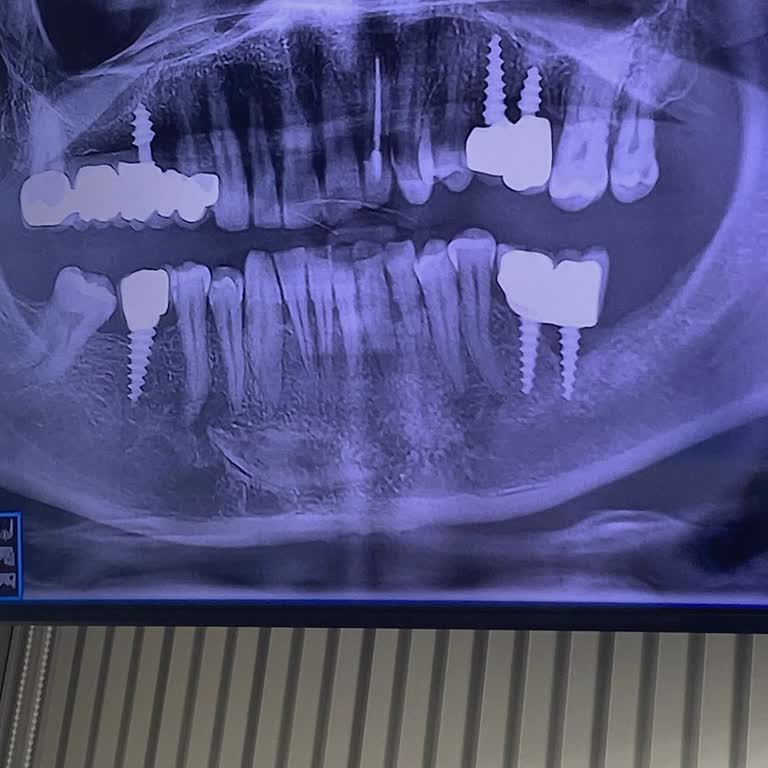

Nevşehir Akdent Ağız ve Diş Sağlığı Kliniği’nde 11 Temmuz tarihinde üç dişime dolgu, bir dişime de kanal tedavisi yapıldı. Ancak işlem sırasında dişlerimdeki çürükler tamamen temizlenmeden dolgu yapıldığını sonrasında aynaya baktığımda fark ettim. Bunu gördüğümde, işlemimi yapan ve isminin K**** old...